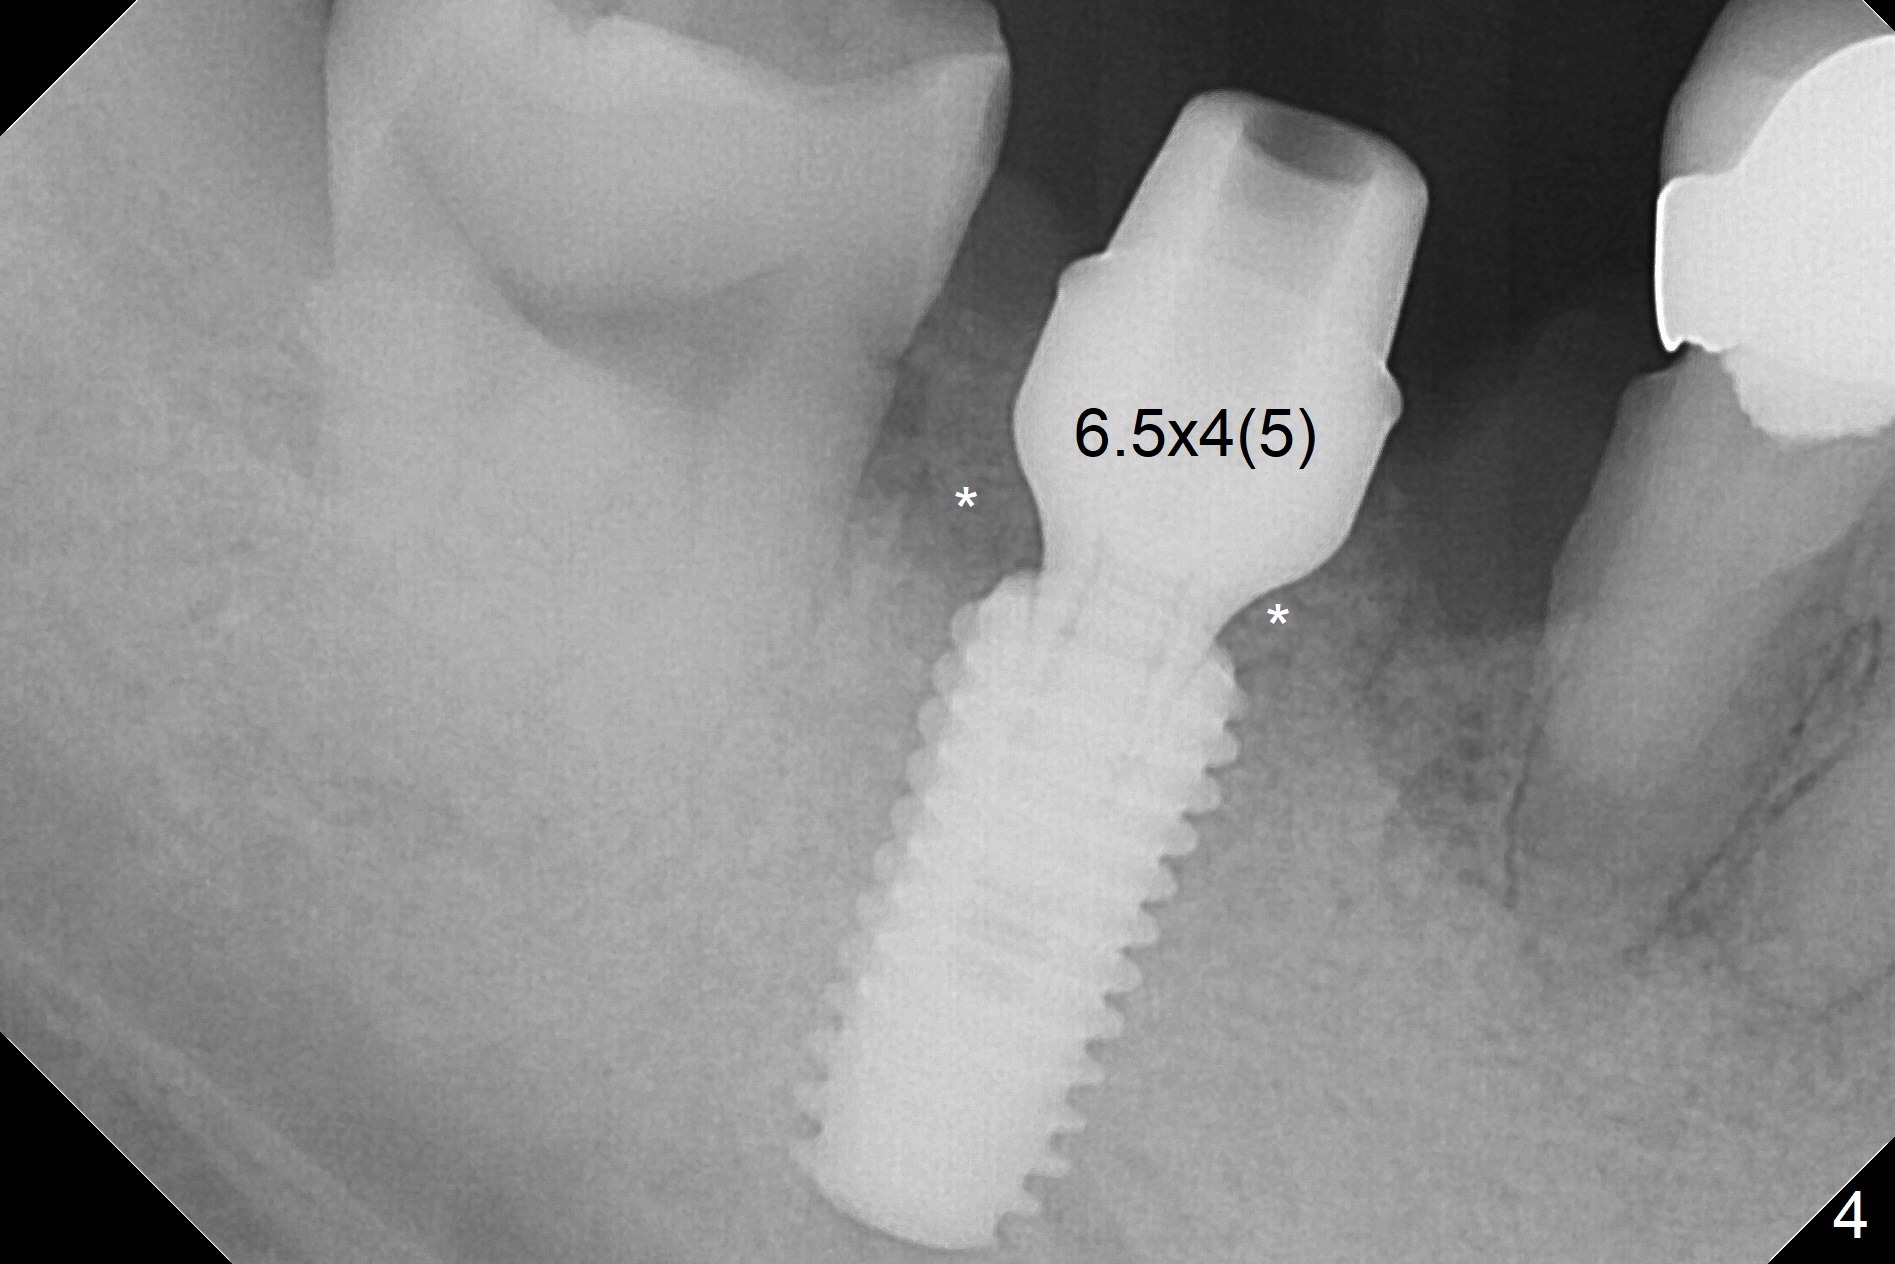

Although the tooth #30 has distobuccal root exposure (Fig.1 <), it is asymptomatic. In contrast the tooth #31 with the distoocclusal caries (*) is symptomatic. After use of 2 mm drill for 18 mm (lingual gingival margin), a calculated parallel pin is inserted (Fig.2 (D: 2 distal roots of the tooth #30)). It appears that a 11.5 mm long implant is appropriate for the site; a 5 mm cuff is expected. Following 4.8 mm drill, a 5.5x11.5 mm implant is placed initially (Fig.3) with an apical space (*) and clearance from the Inferior Alveolar Canal (red dashed line). The implant is placed deeper with placement of a 6.5x4(5) mm abutment and bone graft (*, Fig.4,5). After placement of collagen membrane over the graft, an immediate provisional is fabricated (Fig.6 P) with clearance from the opposing tooth (Fig.7 *). There is no bone loss 3.5 months postop (Fig.8). In fact the abutment has not been seated completely since its placement (Fig.4,5,8). The crown/abutment dislodges 3 years 3 months post cementation (Fig.9). The latter occurs for long incubation time because of opposing partial denture (Fig.10). After trimming proximal surfaces (Fig.11: arrowheads), the abutment remains incompletely seated (Fig.11) due to possible crestal bone interference (Fig.11 *). The smaller abutment by itself remains unseated (Fgi.12). One size small one is completely seated (Fig.13). Impression is taken. Two weeks later the abutment margin is supragingival. After screw torque at 20 Ncm, the crown is cemented with access hole. Excess cement is removed.